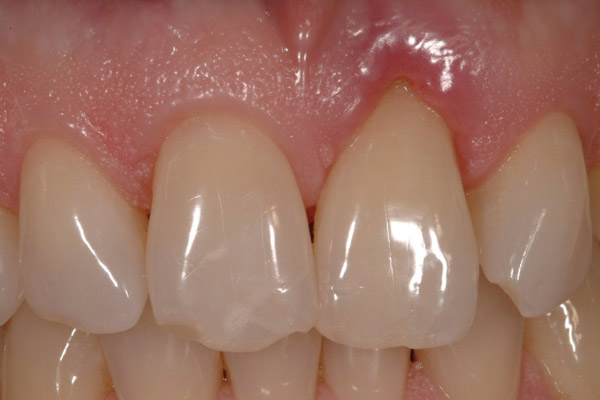

Figure 4  Final restoration of implants in the Nos. 8 and 9 sites 3 years after placement. Note the short central papilla regardless of the presence of bone. Restoration courtesy of Dr. Alan Goldberg.

Figure 4

Figure 5  A naturally low smile line hid the clinical “black triangle” from view.

Figure 5